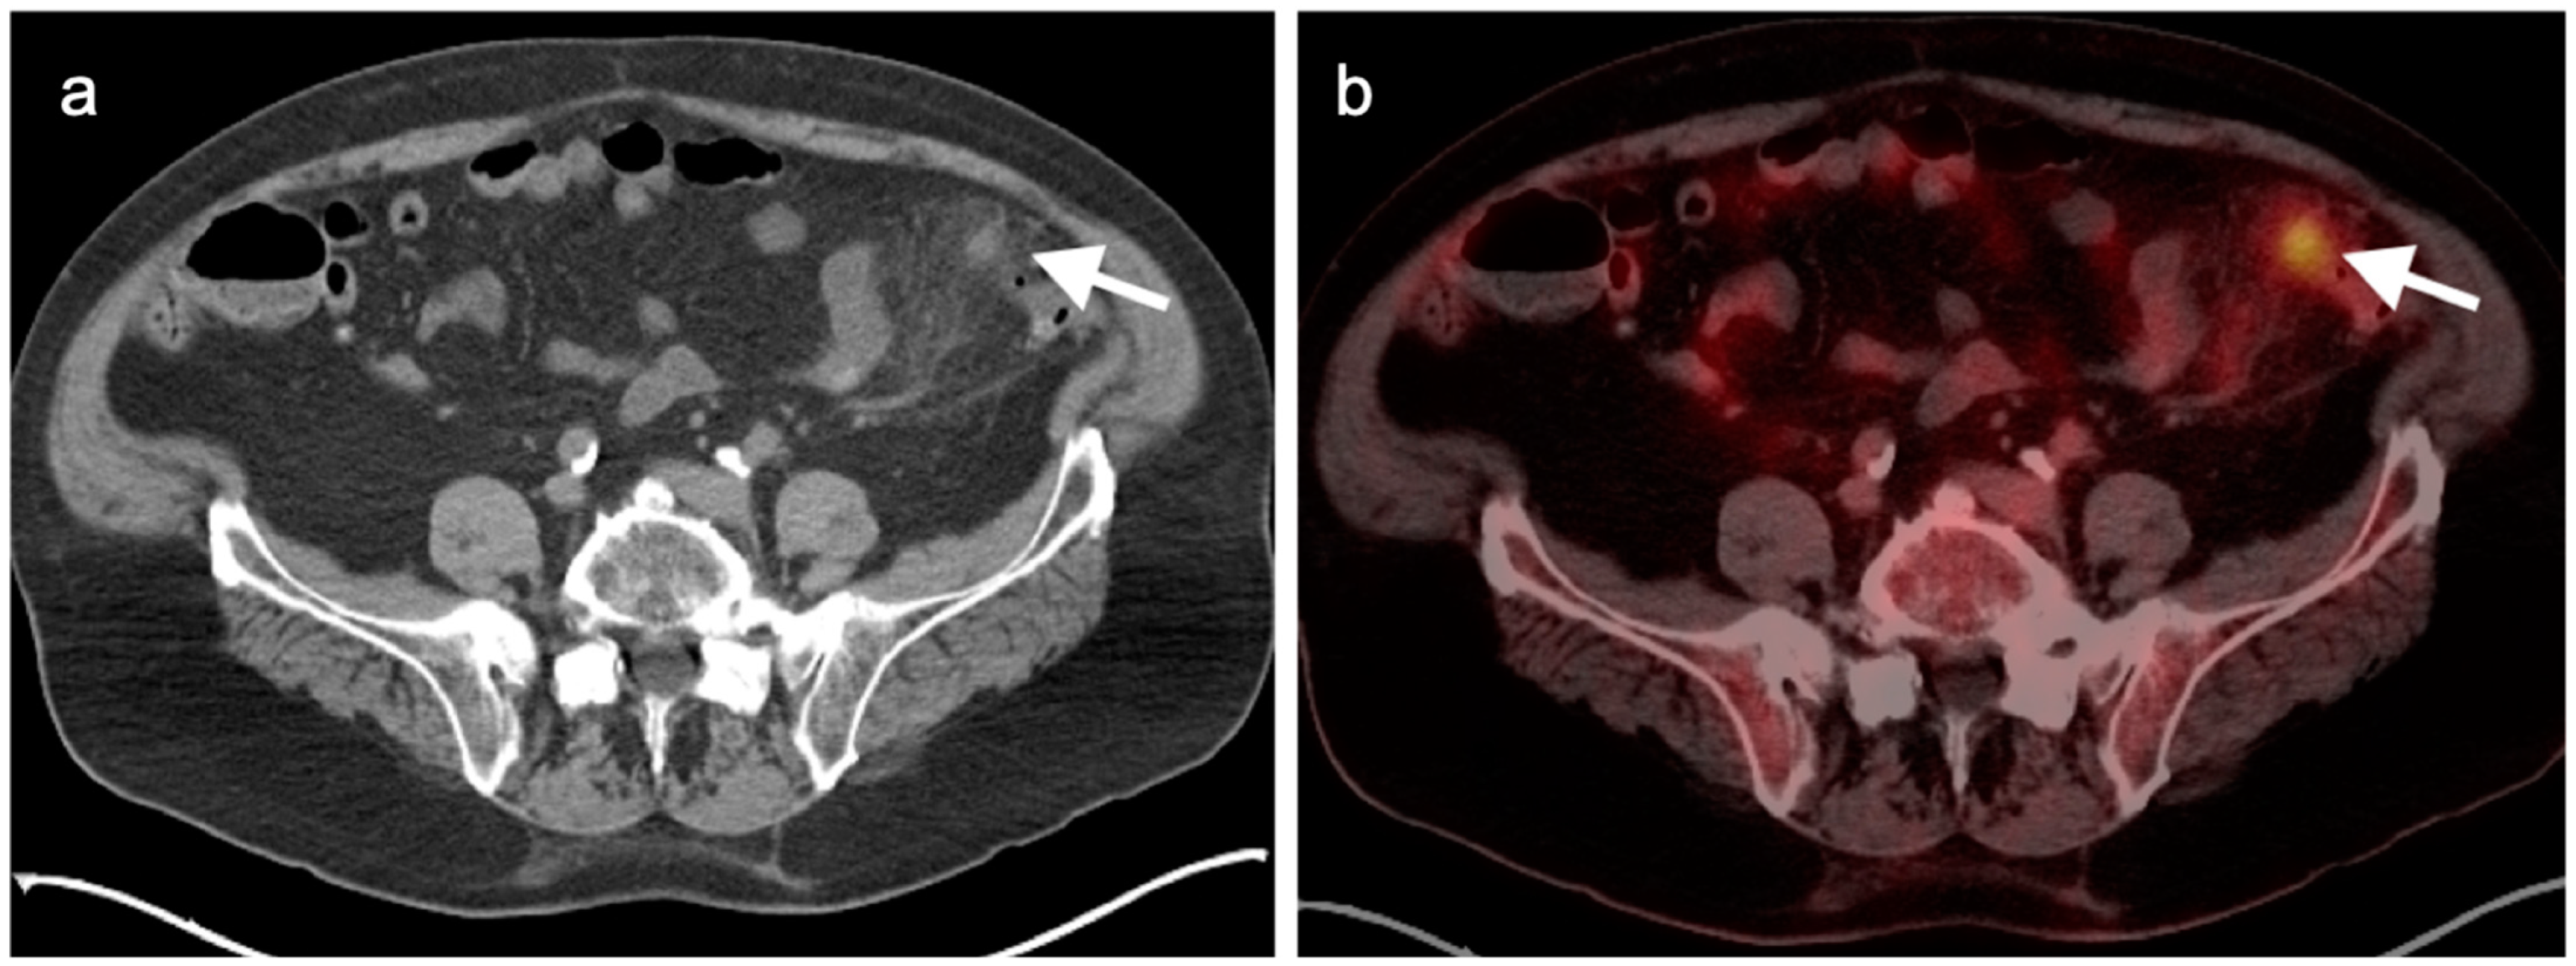

9. Bowel Adenocarcinoma: Colon, Rectum, Small Bowel